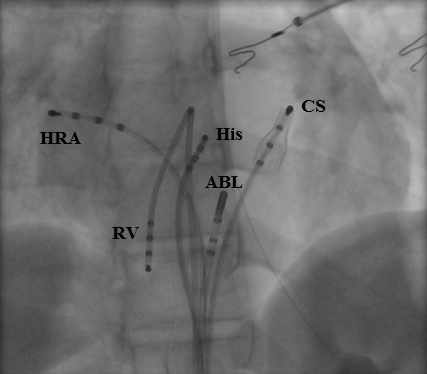

A 19-year-old female underwent repair of complex congenital heart disease (atrial and ventricular septal defect with a criss-cross atrioventricular relationship) in infancy. Because or recurrent palpitations she underwent an electrophysiology study. Atypical atrioventricular nodal reentrant tachycardia was diagnosed. Catheter ablation was performed successfully using cryothermal energy. The diagnostic and therapeutic approach is discussed.